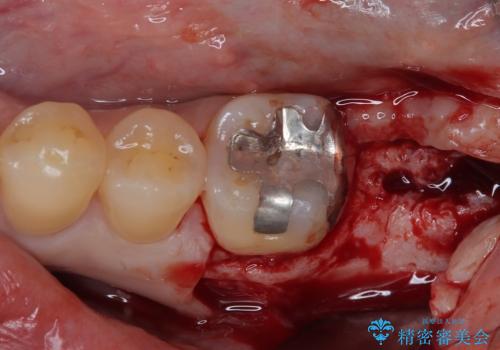

上顎の奥歯は、左右ともに外側に転位しており、特に右上はむし歯の範囲が広く、根管治療も必要な状態でした。

左下の奥歯は状態が非常に悪く、保存は困難と判断されたため、インプラントによる補綴治療が必要でした。

上顎左右の歯をアンカースクリューを用いた部分矯正により位置を修正し、オールセラミッククラウンにて補綴治療を行うこととしました。